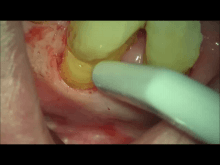

精密根管治療(マイクロエンド)